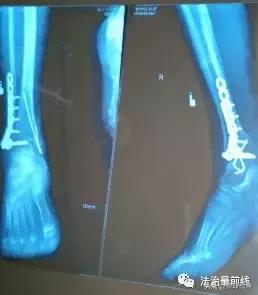

2018年8月28日上午,李女士被推进手术室。手术后,李女士脚踝的右内踝和右外踝处分别留下了约7厘米和11厘米的手术切口,并使用了螺钉、钢板等内固定物。

李女士说,手术一周后,她出院了,“出院前,医生还给她的右脚拍了一张X光片,并告诉我一切正常。”

在家人的建议下,李女士先后到重庆市南川区南坪卫生院、綦江县人民医院复查,两家医疗机构给出的结果都一样:有螺钉放错了位置。

李女士告诉记者:“这两家医院的医生都说,是螺钉打到关节里面去了,还有这两个眼不该钻的,骨头那两个眼,不该钻的都钻出来了。”

提交申请后,李女士立即转院到广西骨伤医院进行治疗。广西骨伤医院提供的入院记录显示:“腓骨远端可见两枚螺钉穿入右踝关节面”且“术口感染”“钢板外露”。医生说,“两枚穿入踝关节的螺钉”是李女士病情恶化的主要原因。

鉴定书认为,患者术后出现伤口感染及不愈合的原因,一是损伤程度,二是手术时机选择欠妥,三是医方手术失误,将右外踝远端两枚螺钉置入关节内,造成患者目前右踝关节创伤性关节炎、关节僵硬、关节功能严重障碍、右侧内外踝骨折延迟愈合。南宁市医学会认为,“此病例属于三级乙等医疗事故,医院方承担主要责任”。

院方对鉴定结果中的“手术时机选择欠妥”、以及“内固定螺钉进入关节腔”存疑。院方认为,“可确认当时并无螺钉进入关节腔”、“术后影像学诊断仅作为参考,术后外院取出螺钉也并无法确认螺钉是进入了关节腔”。